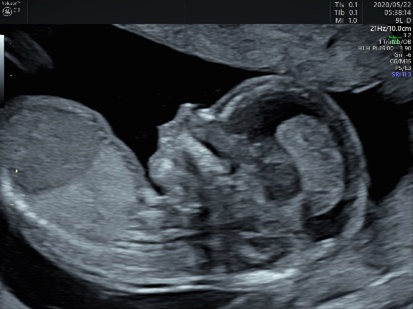

妊娠初期超音波検査は妊娠11週~13週の時期に行う、FMFのプロトコールに沿って詳細に行う超音波検査です。

まず、胎児の頭からお尻までの長さ(CRL)を計測して週数相当であることを確認すると同時に、解剖学的に大きな変化が胎児に認められ無いかどうかを診ていきます。

解剖学的な評価では、以下のような項目を一つ一つ診ていきます。

妊娠初期超音波検査を行う時期のCRLは45mmから84mm程度ですが、超音波機器の発達により詳細な解剖学的な所見を得ることが可能です。